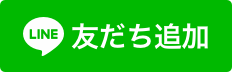

CO

初期段階です。虫歯菌によって歯の表面にあるエナメル質がわずかに溶かされているだけで、まだ痛みや知覚過敏といった症状は出てきません。見た目にもあらわれにくいので、ご自身ではなかなか気づくことができません。この段階では、適切な歯みがきやフッ素塗布で治癒する可能性があります。

C1

COからさらにエナメル質が溶かされ、大きく穴が開いた状態です。冷たいものが染みるようになります。また、穴が空いた箇所が黒っぽく変色しはじめ、見た目にも変化があらわれるようになります。この段階では、虫歯菌が感染した箇所を削ったり、虫歯菌によって空いた穴をレジン(歯科用プラスチック)で埋める処置を行います。

C2

C1からさらに進行し、エナメル質の内側にある象牙質まで溶かされた状態です。象牙質が露出したことでより刺激が神経にまで伝達されやすくなり、冷たいものがしみる場合もあります。この段階では、虫歯菌が感染した箇所を削り、詰めもので蓋をする処置を行います。